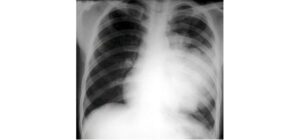

Tràn dịch màng phổi là gì?

Tràn dịch màng phổi là gì? Tràn dịch màng phổi ThS.BS. Nguyễn Hồng Đức Nguyên Trưởng khoa Phòng Khám – Bệnh viện Phạm Ngọc Thạch Cố vấn chuyên môn Trung tâm điều trị bệnh hô hấp Phổi Việt Mỗi lá phổi trong lồng ngực được bao quanh bởi 2 lớp màng rất mỏng gọi là […]